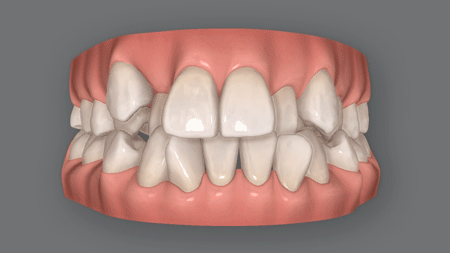

オープンバイトとも呼ばれる開咬(かいこう)は、奥歯で噛んだときに上下の前歯閉じず隙間空いてしまう症状です。

(1) 前歯沈み込んでいる

前歯が骨の中に沈み込んで開咬

爪を噛む癖のある人、子供の頃に指しゃぶりの癖があった人は、前歯が顎の骨の中に沈み込んでしまい、上下の隙間が空いてしまうことあります。

前歯が外側に傾いて開咬に

前歯を舌で押し出す癖がある人や、子供の頃に指しゃぶりの癖があった人は、前歯が外側に斜めに傾いてしまうことがあります。

その結果、上下の間に隙間が空いてしまい、開咬となるのです。